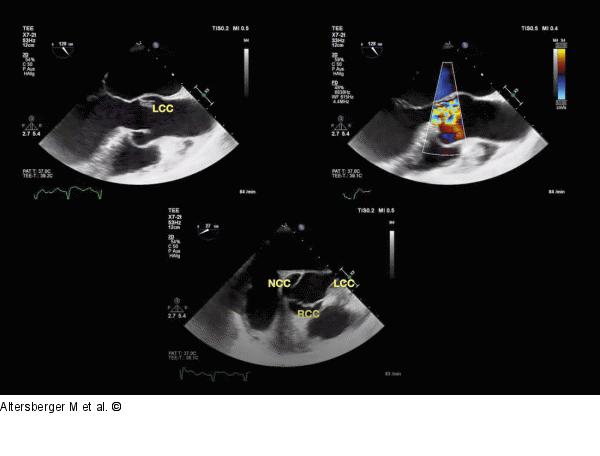

Abbildung 4: TEE - LCC TEE-Studie mit Beschriftung der anatomischen Strukturen der Aortenklappe in der kurzen und der langen Achse midösophageal eingestellt. Das LCC hierbei rupturiert. |

TEE-Studie mit Beschriftung der anatomischen Strukturen der Aortenklappe in der kurzen und der langen Achse midösophageal eingestellt. Das LCC hierbei rupturiert. |